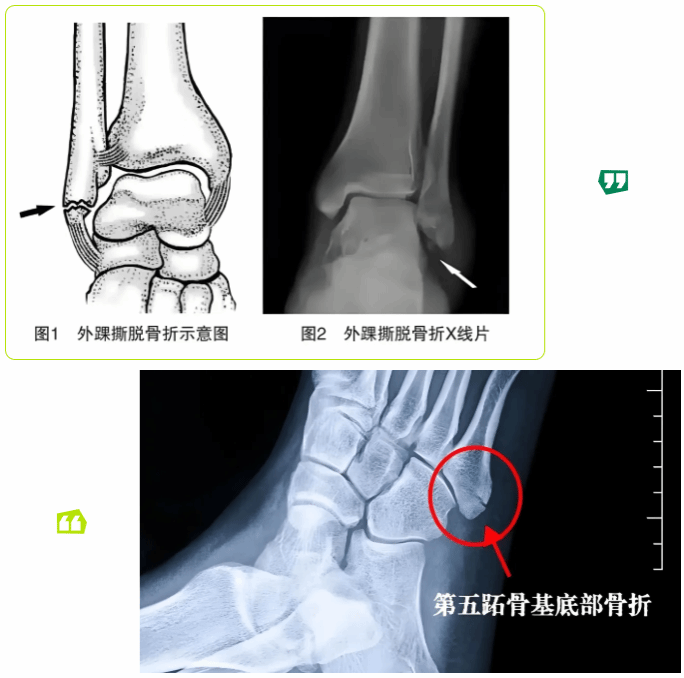

医生介绍,影像学检查是鉴别此类骨折的“金标准”。从小王拍摄的踝关节正侧位片和足正斜位片可以看到,他的右外踝尖有一绿豆大小的撕脱骨片,移位约2mm,符合外踝撕脱性骨折。第五跖骨基底部有一条清晰的骨折线,骨折块无明显移位,符合第五跖骨基底部Ⅰ型骨折。

值得注意的是,外踝撕脱性骨折在临床诊断中存在较高的漏诊风险。一是因为外踝撕脱性骨折的骨片可能极小,普通踝关节正位片易被软组织阴影遮挡,需结合侧位片观察(必要时需要CT检查更清楚)。另外,第五跖骨基底部骨折若仅拍踝关节片(未拍足正斜位片),很可能漏诊,因为第五跖骨基底部在踝关节片中显影不清。再者,早期肿胀明显时,骨折线可能被血肿掩盖,需1-2周后复查X线才能清晰显示。